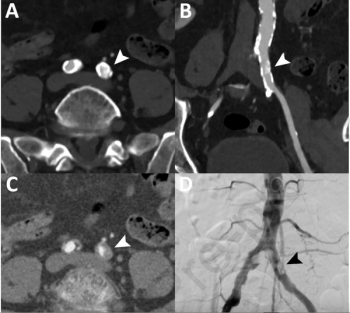

In recent interviews, Eric Rohren, M.D., and Krishna Nallamshetty, M.D., discuss the potential of abdominal aortic aneurysms (AAAs) to progress into life-threatening consequences and an emerging AI-powered tool that may bolster adherence to best practice recommendations in radiology reporting of incidental AAA findings on CT and MRI.